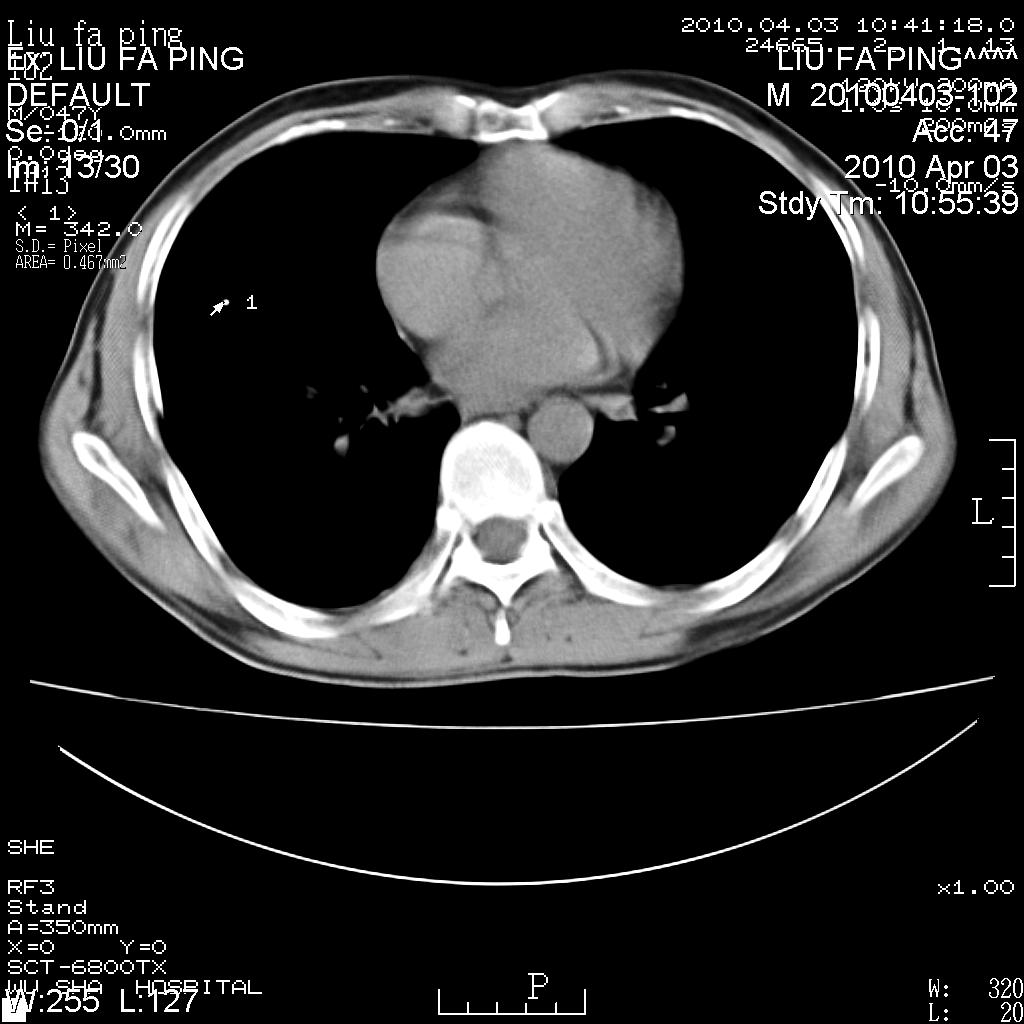

标题: CT25875:咳嗽数天。

平时身体健康,无不适

男性47岁,考虑中心性肺癌合并阻塞性肺炎,纵膈淋巴结肿大。肺内及纵膈淋巴结钙化。

建议支气管镜检

支持右侧中央型肺癌伴右肺上叶阻塞性炎症、纵膈淋巴结转移,建议纤支镜检查!

男性47岁,考虑中心性肺癌合并阻塞性肺炎,纵隔淋巴结肿大。肺内及纵隔淋巴结钙化。

考虑右肺中央型肺癌并阻塞性肺炎,右肺门及纵隔淋巴结转移;建议必要时行纤支镜检查进一步明确诊断。